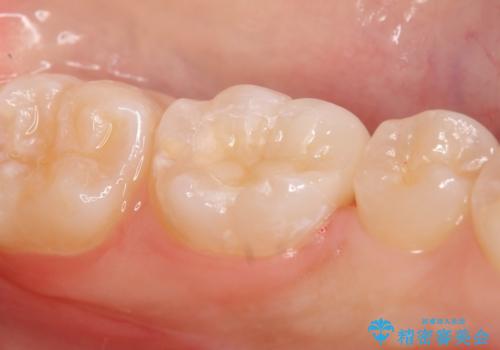

- 左下奥歯がしみるので診て欲しいといらっしゃった方の症例です。

古い樹脂と虫歯を除去後、セラミックインレーによる修復を行いました。

当院のセラミックインレーはemaxという強度と審美性に優れた材料を使用しています。

またプレス方式でインレーを製作しているため、削り出しで製作するCADCAMより優れた適合性も持ち合わせており、虫歯が再発しにくい修復物です。